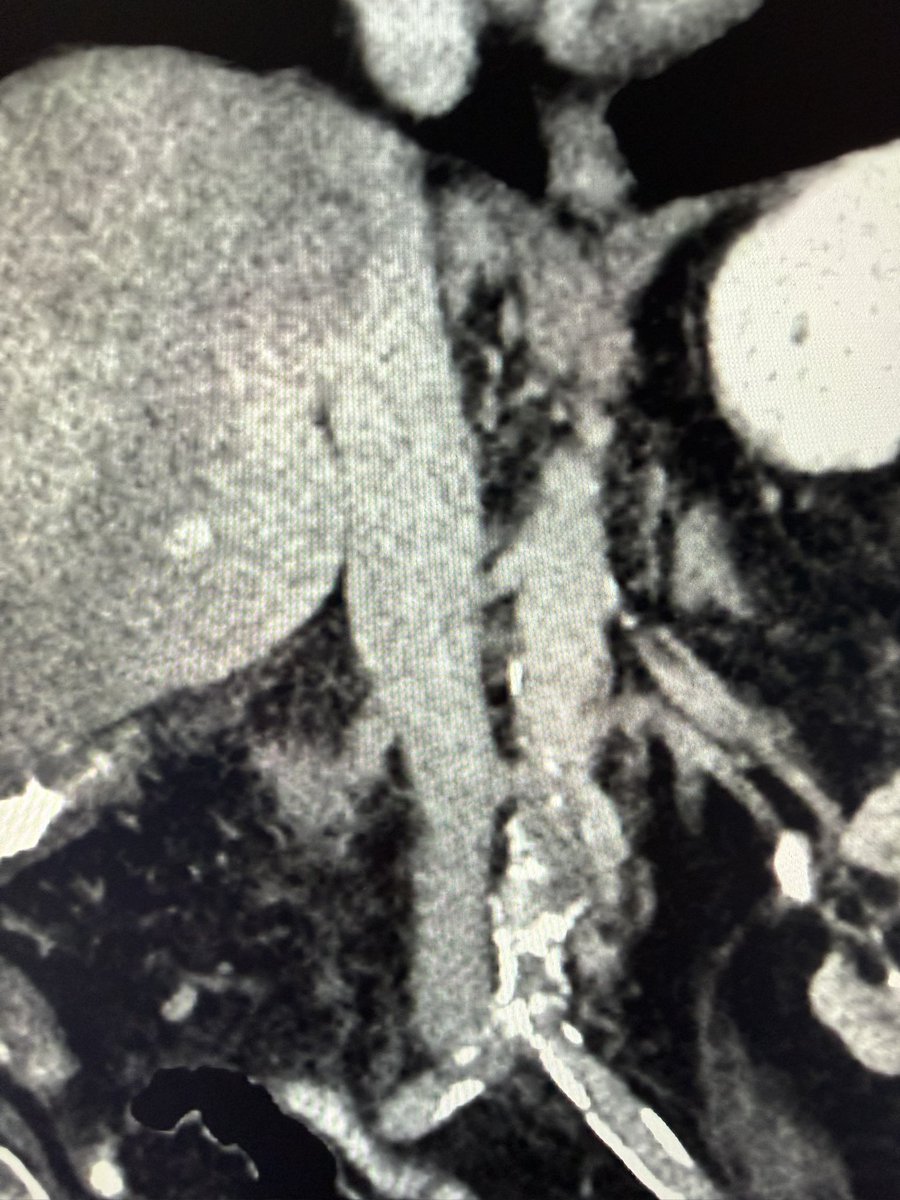

Large volume IVC thrombectomy and mod sed TIPS done same session - patient was able to be discharged and make it to her sons wedding - she fit much better into her dress with no ascites!